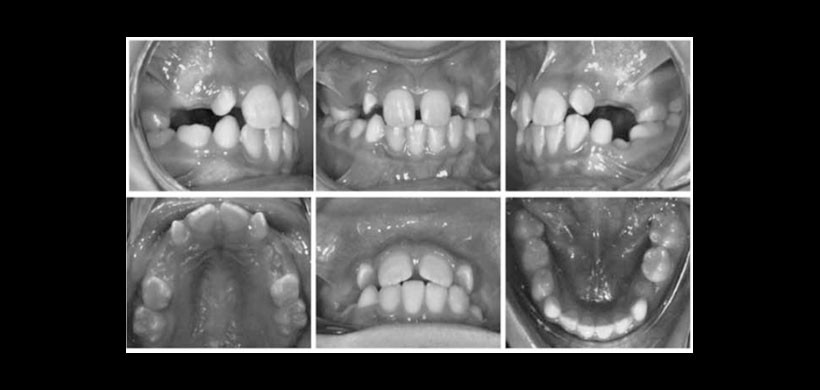

Al examen clínico se observa al paciente en dentición mixta con la pieza 7.4 en infraoclusión severa, con pérdida de espacio evidente y mesioinclinación de las piezas vecinas (Figura 1). La madre relata que la historia clínica del diente afectado ha sido progresiva y que estaba siendo controlada de forma clínica y radiográ ca en otra consulta dental.